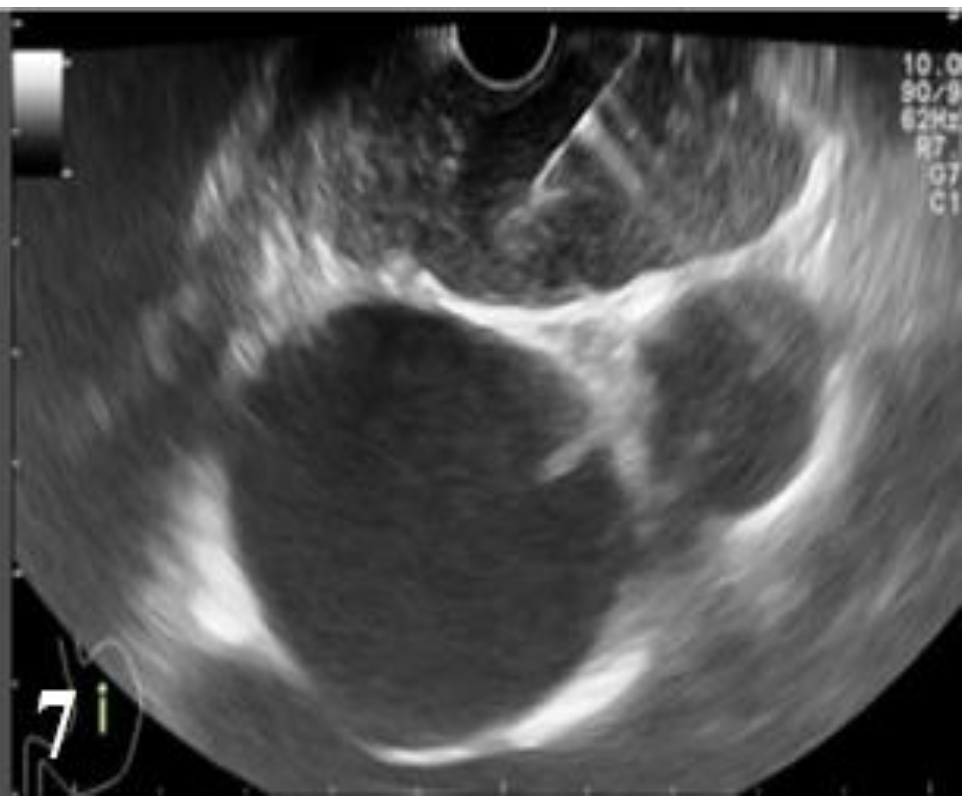

Figure 3.

EUS image showing the lesion that involves all the layers of the distal esophageal wall without invasion into the aorta (T3).